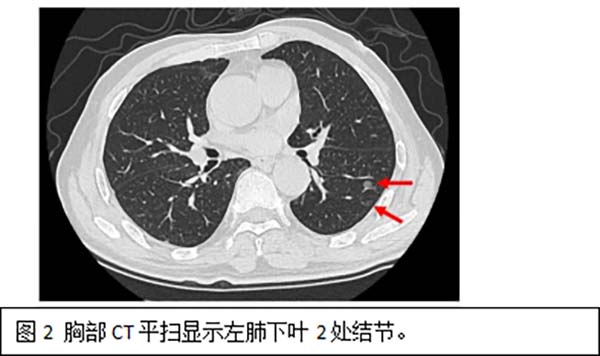

面对如此复杂的病情,胸外一科主任阮军忠带领团队与CT介入科主任王东坡团队进行了深入的术前讨论和准备,患者肺部存在的6个高危结节,直径均在6-10mm之间,分别位于左肺上叶尖后段、前段(图1)及左肺下叶背段(图2),若全部通过外科手术切除,不仅难以准确定位所有结节,还可能需要切除超过一半的左侧肺组织,对患者的生活质量和手术风险都构成严峻挑战。